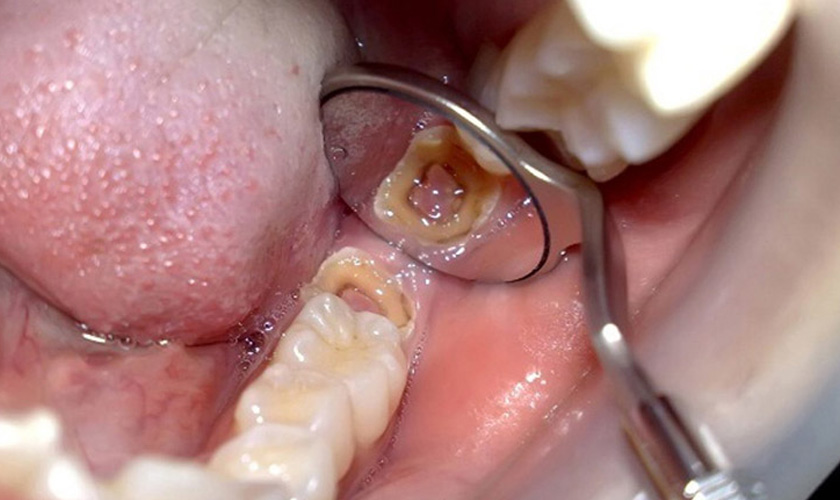

- Sâu răng: Răng khôn ở trong cùng của hàm răng nên rất khó để vệ sinh sạch sẽ, đặc biệt là những răng chỉ mọc lên được một phần hoặc mọc lệch, đâm vào các răng bên cạnh. Điều này khiến cho thức ăn và vi khuẩn dễ dàng tích tụ, lâu ngày sẽ gây ra sâu răng.

Răng khôn mọc lệch có thể dẫn đến tình trạng sâu răng